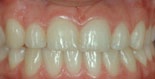

Före behandling av utrymmesanomali (glesställning) Efter behandling av utrymmesanomali (glesställning)

Utrymmesproblem beror på att det antingen saknas tänder, eller att det finns för många, alternativt att käkarna är för små eller för stora. Tänder kan vara trångställda, beroende på att det är ont om plats i käkbenet. Det omvända problemet finns också, det vill säga att tänderna är glesställda så ett mellanrum bildas.